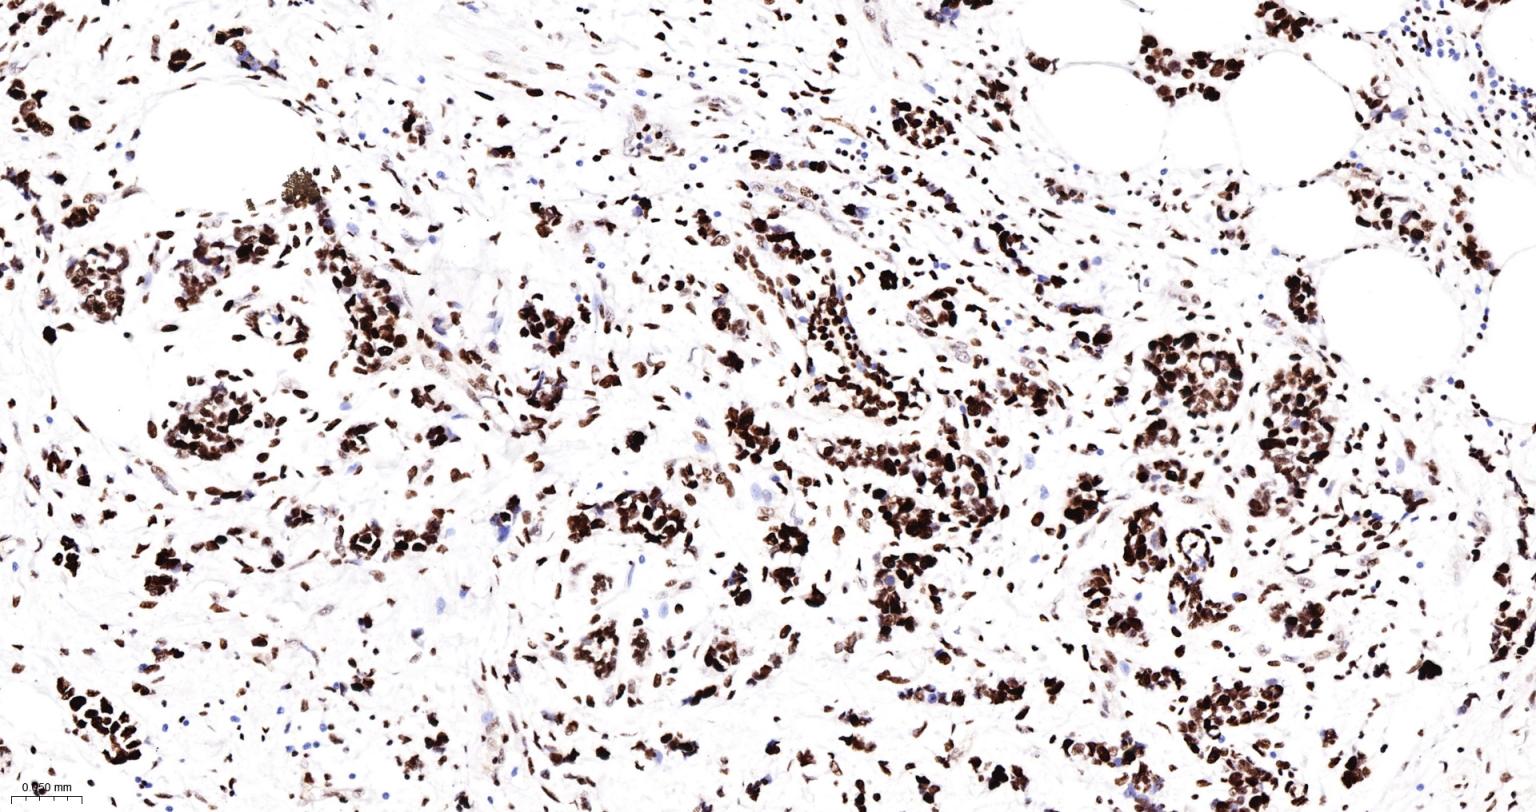

Paraformaldehyde-fixed, paraffin embedded Human Breast Cancer; Antigen retrieval by boiling in sodium citrate buffer (pH6.0) for 15 min; The section was incubated with DDX9 Monoclonal Antibody, Unconjugated (bsm-61787R) at 1:200 overnight at 4°C, followed by conjugation to the bs-0295G-HRP and DAB (C-0010) staining.